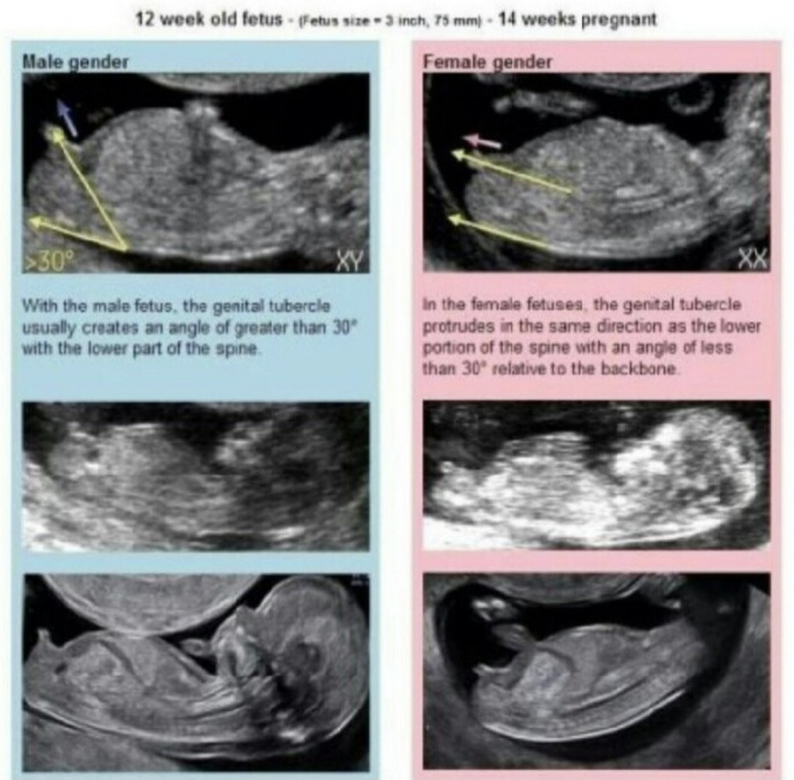

보통 12주가 되면 아기의 눕는 자세로 각도법을 이용하여 성별을 추측하게 됩니다.

나도 내 아기의 성별을 추측할 수 있기를 바랐지만

아기가 눕지 않았고 정밀 초음파 이미지가 너무 흐릿했습니다.